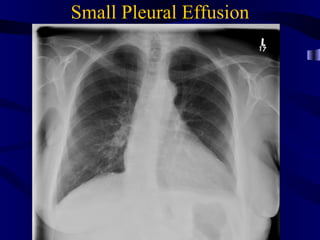

Small Pleural Effusion

Small Pleural Effusion Normal: Sharp Angles Blunted posterior costophrenic sulcus